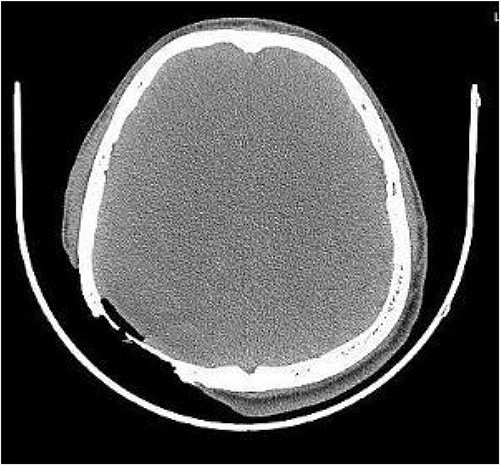

On post-debridement Day 16, the exposed skull was ~8 cm × 9 cm, the bone was dark, and the cortex of the skull defect was ~3 cm × 3 cm (Fig. 1). Computed tomography showed the presence of gas inside the skull (Fig. 2). Bacterial culture of wound secretions reported Proteus mirabilis. During residual wound debridement, a defect of ~1 cm × 1 cm of the inner plate of the skull and dura mater exposure were found (Fig. 3). Subsequently, two skin dilators were embedded under normal scalp and were dilated by regularly injecting saline (Fig. 4). The exposed dura was regularly rinsed with saline to reduce bacterial colonization.

Skull exposure of ~8 cm × 9 cm, the bone being dark, and a cortex skull defect of ~3 cm × 3 cm.